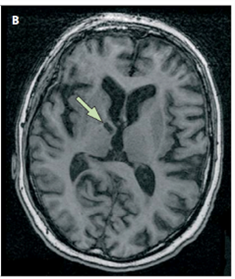

L’artériolosclérose est une maladie des petites artères qui pénètrent dans le cerveau pour le vasculariser (Fig.3). Cette maladie, qui est associée au vieillissement et à l’hypertension artérielle, induit des modifications de la paroi artérielle qui peuvent aboutir à un rétrécissement ou une occlusion de la lumière artérielle ou à une rupture de la paroi. Cette artériopathie peut se compliquer d’infarctus de petite taille (dits lacunaires) (Fig. 4) ou d’hémorragies cérébrales, qui peuvent ou non se manifester par des symptômes neurologiques aigus, en fonction de leur siège et de leur volume.

Fig 4 : Petit infarctus cérébral (flèche) lié à l’occlusion d’une petite artère cérébrale